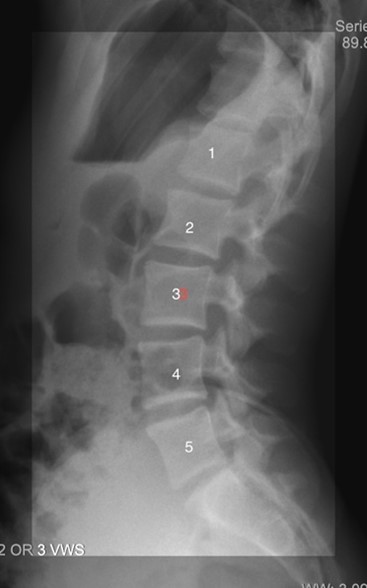

Volleyball bending and rotating movements can put stress on the lumbar vertebrae — the five bones in the lower back between the rib cage and the pelvic bones.

These lumbar vertebrae surround and protect the spinal cord, and certain parts, called the posterior elements, are at unique risk for overload injuries. Repetitive extending and rotating can lead to excessive compression forces on posterior element structures such as the pars interarticularis, pedicles, and articular process/facet joints. The pars interarticularis regions also may have reduced blood supplies during growth spurts, making them even more at risk for overload injuries.Â

Posterior elements of a lumbar vertebrae, image from https://eorthopod.com/lumbar-spondylolysis/